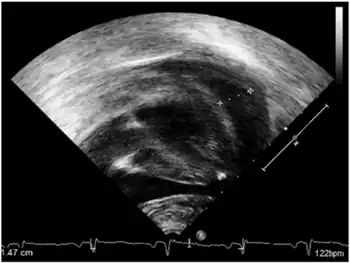

- Early onset-pericardial effusion

- heart arrhythmias